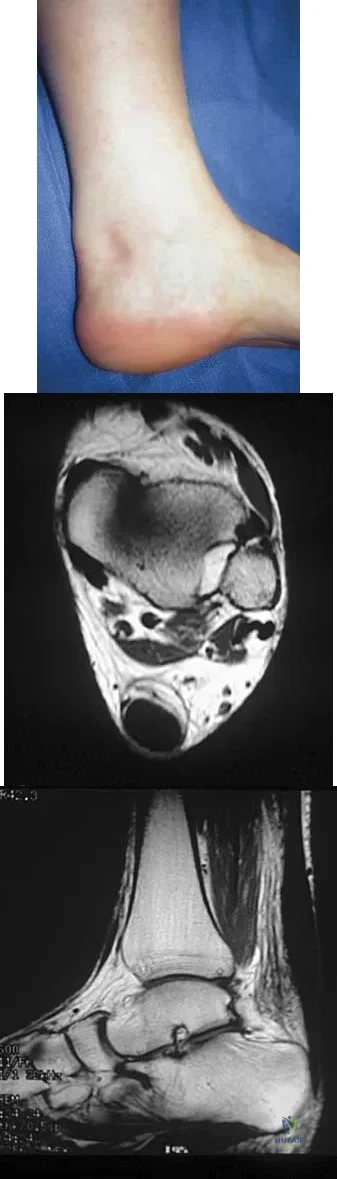

A 35-year-old woman who runs long distance has had posterior calf tenderness for the past 3 months. A clinical photograph is shown in Figure 10a, and MRI scans are shown in Figures 10b and 10c. Management at this point should consist of

Explanation

The initial treatment for peritendinitis should consist of calf stretching in an eccentric mode and physical therapy. In a recent study, this treatment has been found superior to surgical debridement in nonextensive peritendinitis and pantendinitis. A non-weight-bearing cast, while useful in reducing inflammation, will result in calf atrophy and poorly organized collagen repair. Cortisone is contraindicated because of the danger of tendon damage. Tendon debridement at this stage is not indicated. Alfredson H, Pietila T, Jansson P, Lorentzon R: Heavy-load eccentric calf muscle training for the treatment of chronic Achilles tendinosis. Am J Sports Med 1998;26:360-366.